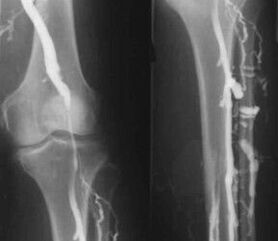

Η πιο κοινή ενόργανη διαγνωστική μέθοδος είναι η χρήση υπερηχογραφικής εξέτασης των φλεβικών αγγείων των ποδιών. Αυτή η τεχνική σας επιτρέπει να απεικονίσετε το αγγειακό σύστημα και να προσδιορίσετε τον βαθμό προόδου της παθολογικής διαδικασίας.

- Φλεβογραφία.